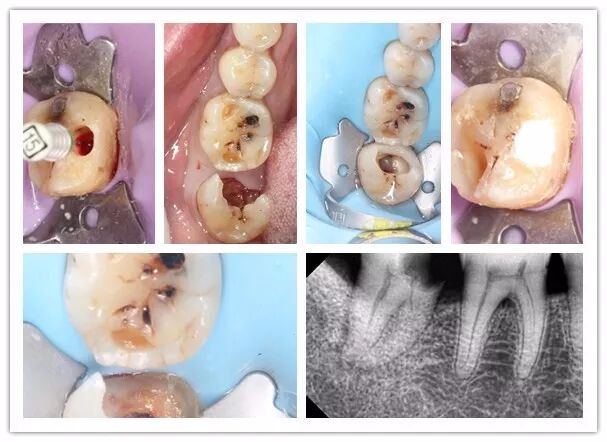

| 11:00-12:00 | 橡皮障的使用方法及注意事项;开髓方法及直线通路的建立;工作长度如何确定及方法 | 左宗波 |

| 14:00-15:00 | 根管预备方法及冲洗方法;根管充填方法及评估 | 左宗波 |

| 11:00-12:00 | 根管治疗术前检查及方案确立;浸润麻醉的实施;术区隔离及洞型恢复;髓腔清理及治疗通路的建立;封药的选择 | 陈希 |

| 14:00-15:00 | 实操演示 | 陈希 |

2012年至2013年于北京天坛口腔医院研修学习热牙胶及修复一年,擅长牙体牙髓热牙胶根管的预备和3d充填,前牙美学修复及复杂阻生牙的微创拔。

宇森医疗特聘讲师,各地开展根管内训,已赴福建、新疆、广州等地开展根管公开课。